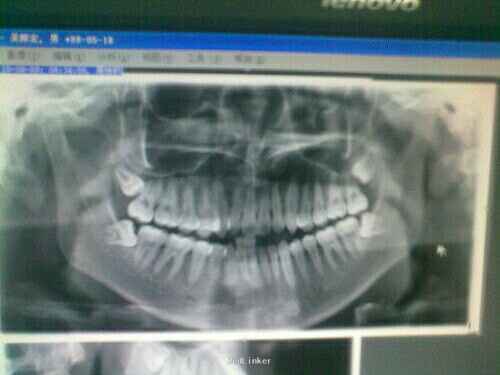

检查:18咬合面牙龈瓣比较大,覆盖牙冠远中一部分。探痛(-),叩(+),探牙龈出血,松动度无,冷热刺激无不适。口内咬合正常。拍口腔X光线片示:18垂直中位。

诊断:18垂直阻生